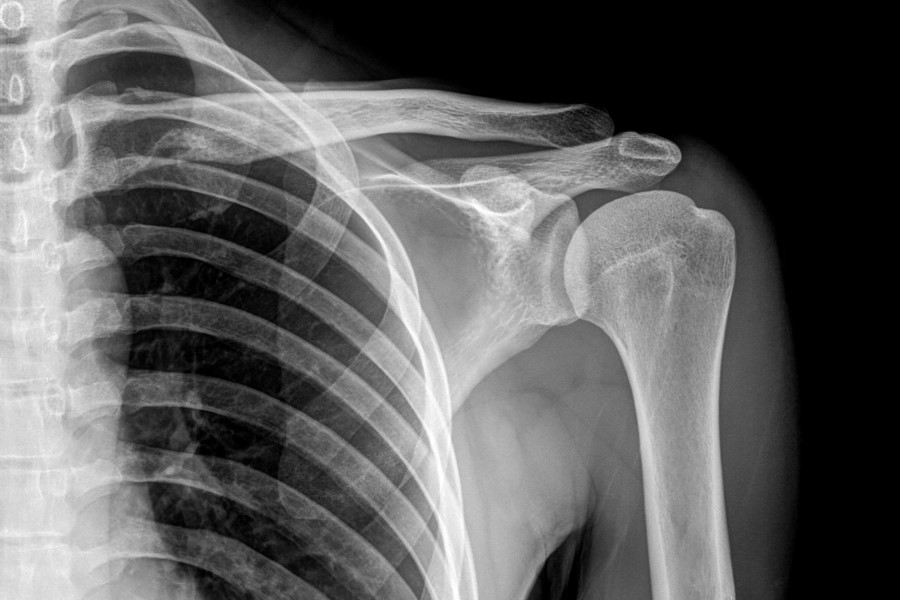

Sklerotyzacja podchrzęstna to termin określający zmiany destrukcyjne w obrębie warstwy podchrzęstnej kości, powstające w miejscach największych przeciążeń narządu ruchu. Na skutek ubytku chrząstki stawowej i zwiększenia tarcia między powierzchnią stawów wywołanych brakiem amortyzacji, organizm stara się zrekompensować ubytki chrząstki nadbudowując w tych miejscach kość. Proces sklerotyzacji bardzo często towarzyszy chorobom zwyrodnieniowym stawów, takim jak reumatoidalne zapalenie stawów (RZS). Sklerotyzacja zachodzi najczęściej w obrębie stawów krzyżowo-biodrowych, kręgosłupa, stawu biodrowego, kolanowego czy barkowego.

Najważniejszym narzędziem diagnostycznym w przypadku chorób zwyrodnieniowych stawów związanych z występowaniem sklerotyzacji jest badanie obrazowe - RTG. Za jego pomocą lekarz, zazwyczaj reumatolog, jest w stanie określić stopień zaawansowania i rodzaj sklerotyzacji.